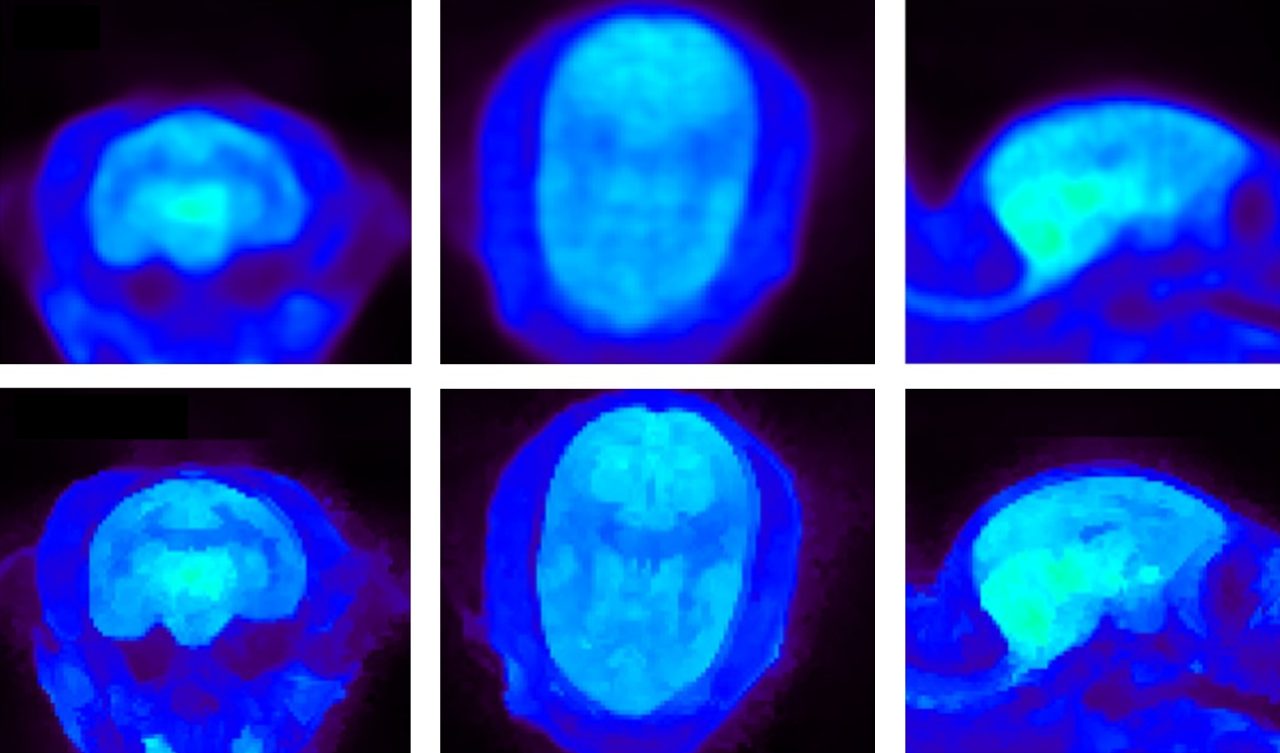

PET検査の改善

• 最も一般的な同位体を簡単に選択できる包括的な同位体データベース

• 解剖学的MRIを活用したBowsher Prior再構成によるPET画像の改善

• コールドカラーパレットを含むカラールックアップテーブルの拡張により、視認性が向上。

PET FDGによるマーモセット脳イメージング。上:MAP再構成。下: 高度なPET再構成アルゴリズムであるBowsher Prior再構成。 提供:S. Valable and M. Naveau, Cyceron, Caen, France: S. Valable and M Naveau, Cyceron, Caen, France.